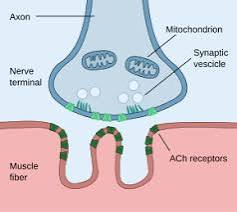

Neuromuscular Junction (NMJ)

The synapse between a motor neuron and a skeletal muscle fiber.

Acetylcholine (ACh)

Released from synaptic vesicles; diffuses across the synaptic cleft and binds to ACh receptors, initiating a muscle action potential.

Acetylcholinesterase

Breaks down ACh.